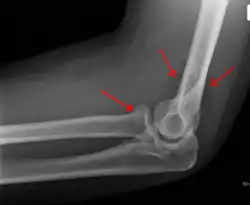

Anterior sail signs as well as posterior fat pad in a child with a supracondylar fracture.